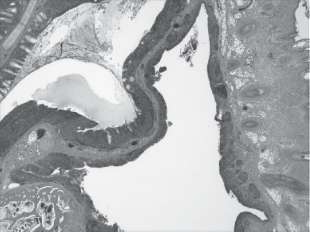

Microscopic pathology: Microscopic pathology caused by M. gallisepticum infection in chickens and turkeys is characterized by marked thickening of the mucous membranes of affected respiratory tract tissues as a result of infiltration with mononuclear cells (primarily lymphocytes) and lymphoid follicle hyperplasia. Metaplasia of the respiratory epithelium from pseudo‐stratified ciliated columnar to nonciliated low cuboidal or squamous has been described. Increased tracheal mucosal thickness is commonly used as a measure of M. gallisepticum disease severity. Lungs may have pneumonic areas, lymphofollicular changes, and granulomatous lesions. Detailed examinations of M. gallisepticum‐infected chicken air sacs via light microscopy, scanning electron microscopy, and histomorphometric evaluation have been published. Keratoconjunctivitis in layer chickens associated with M. gallisepticum infection is characterized by epithelial hyperplasia, marked lymphocytic infiltration with the formation of germinal centers, and subepithelial edema, resulting in marked thickening of the eyelids.

Histologic examination of turkey brains in cases of encephalitic M. gallisepticum revealed acute to subacute encephalitis with lymphocytic cuffing of vessels, vasculitis, focal to multifocal parenchymal necrosis, and leptomeningitis. Salpingitis associated with reduced egg production in layer chickens was characterized by marked thickening of the oviductal mucosa caused by epithelial hyperplasia and marked lymphoplasmacytic infiltration (McMullin 20

Figure 6. Microscopic pathology of chickens infected with M. gallisepticum